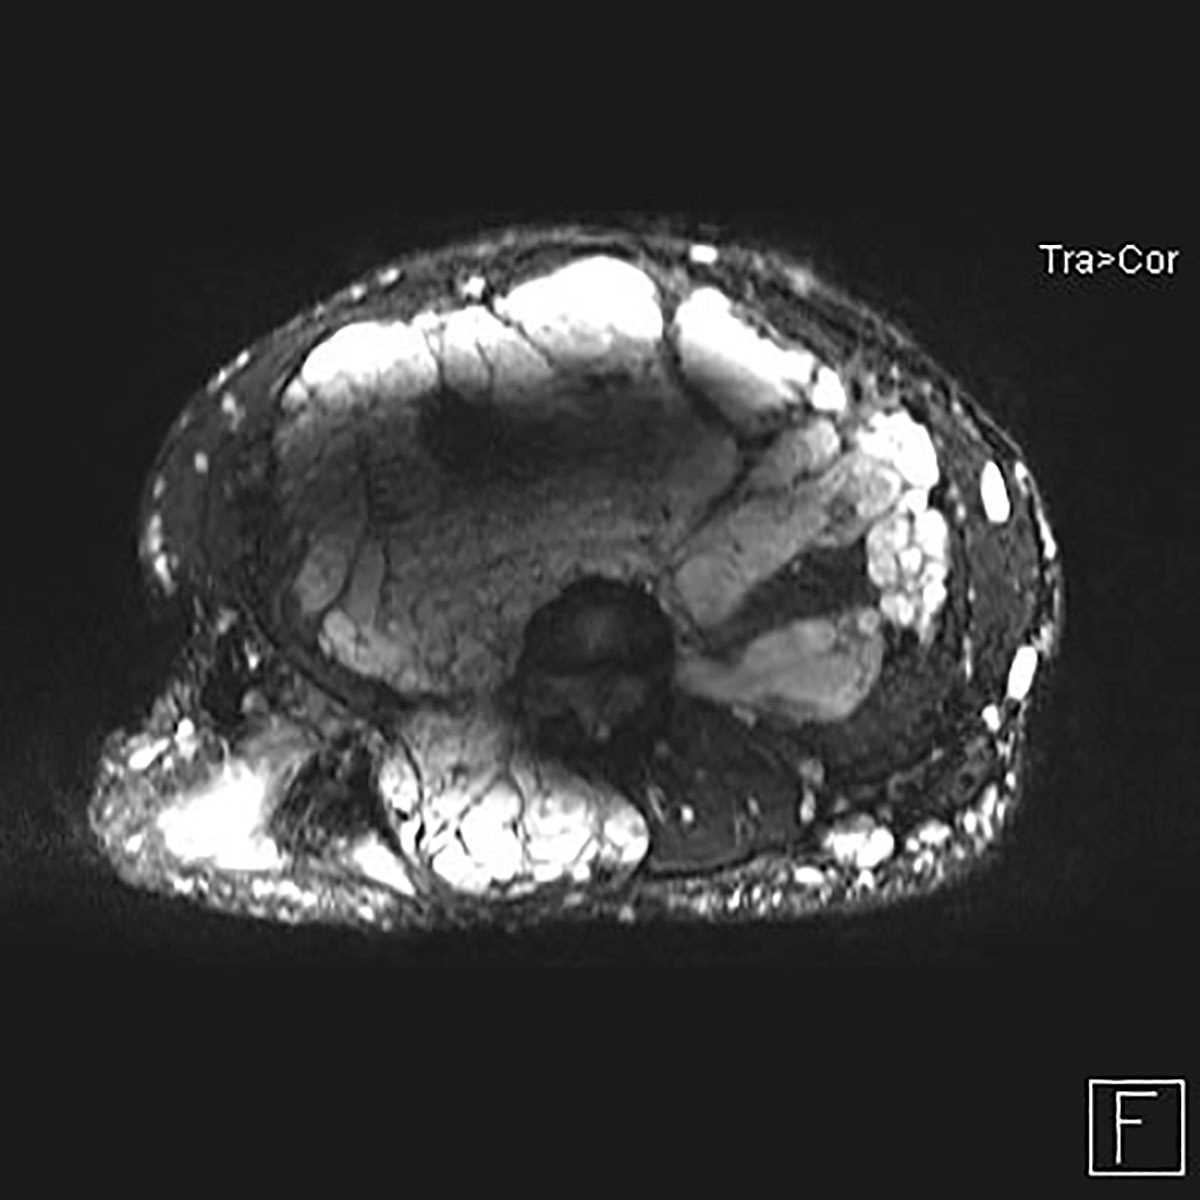

Krukenberg tumors of ovaries

Multiple MR images demonstrate bilateral masses in the ovaries, each of which demonstrates restricted diffusion, found to represent Krukenberg tumors in this patient with a primary gastrointestinal malignancy